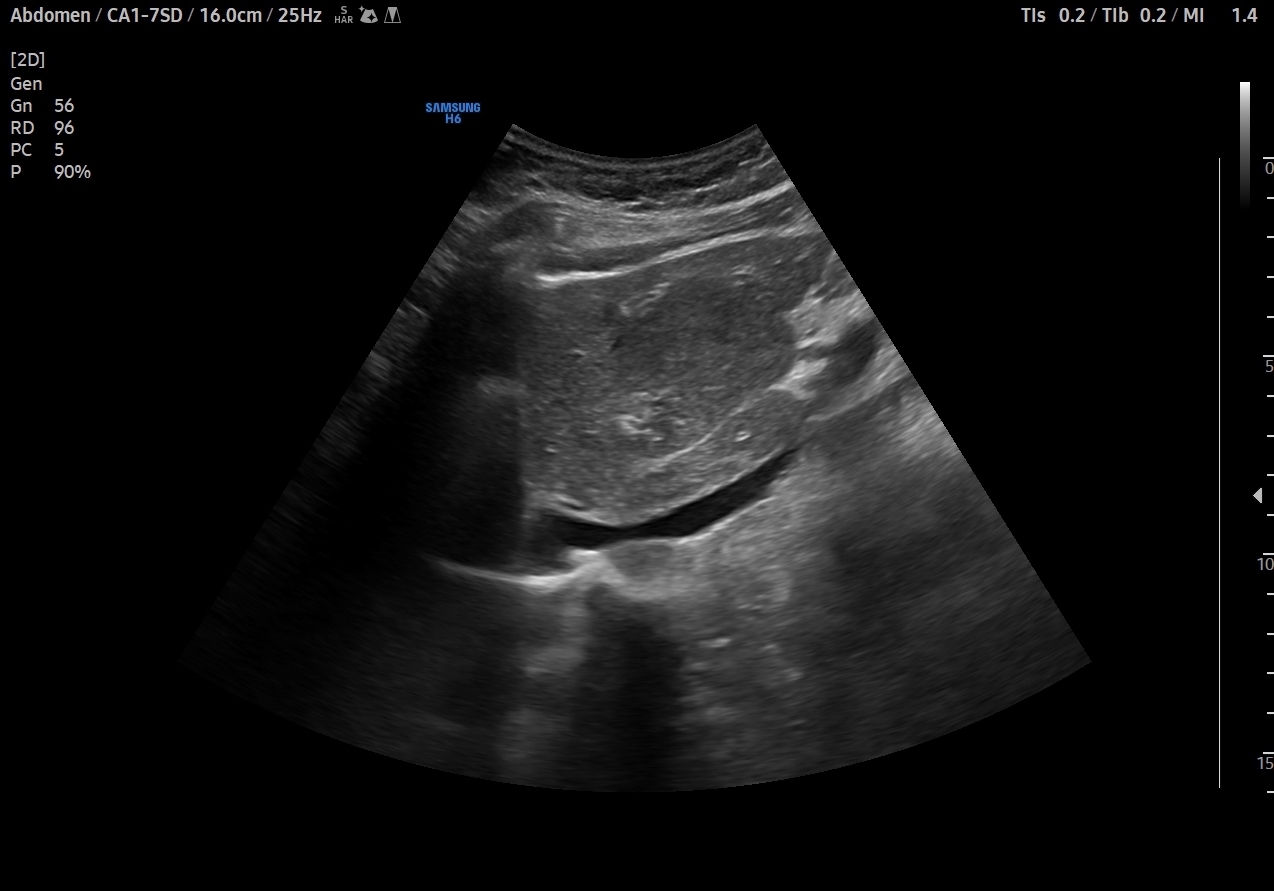

En el lóbulo hepático izquierdo visualizamos lesión focal iso-hipoecogénica respecto al parénquima hepático circundante que mide 4,6 x 4,5 x 3,9 cm y que presenta un aumento de la señal Doppler. Vemos la imagen tanto en cortes transversales como en cortes longitudinales, también con el modo Doppler activo. Resto de parénquima hepático y vía biliar de aspecto normal, sin otras alteraciones.